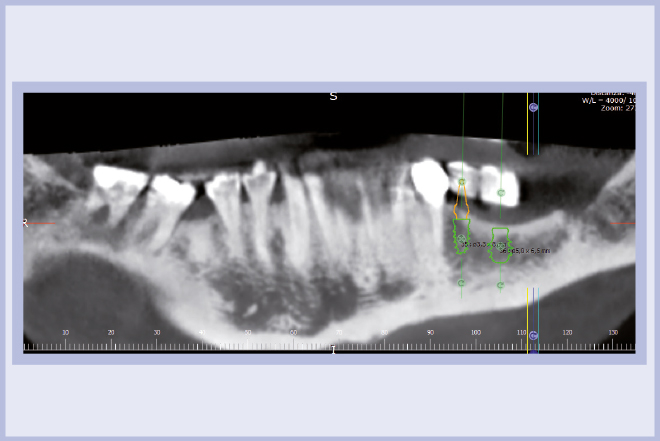

Per riabilitare la masticazione del terzo quadrante, con osso gravemente atrofico, si procede allo studio del caso con esame radiologico 3D e posizionamento virtuale di impianti Exacone® Leone. La prima valutazione è stata eseguita con il software dell’apparecchio radiografico Cone Beam presente in studio. Dopo aver verificato che la quantità di osso residuo fosse sufficiente all’inserimento di due impianti, seppur di dimensioni ridotte, in sede 3.5 e 3.6 senza l’ausilio di tecniche di rigenerazione ossea (Figg. 1-3), si richiede al laboratorio di confezionare una mascherina radiologica con ceratura diagnostica radiopaca e repere standardizzato a livello incisale come da protocollo Leone (Figg. 4, 5). Si verifica quindi clinicamente l’assenza di mobilità della mascherina dopo il posizionamento nel cavo orale del paziente (Figg. 6, 7). Si effettua una CBCT con la mascherina in posizione e l’esame viene inviato in formato DICOM all’azienda Leone assieme al modello master della paziente. L’azienda provvede quindi ad inviare agli Autori il software 3Diagnosys (software di progettazione) in licenza monopaziente con caricati i file DICOM ricevuti; il software viene quindi utilizzato per la progettazione definitiva del caso (Figg. 8-12).

- Figg. 1-3 – Esame Cone Beam iniziale, si verifica la fattibilità di inserimento impianti

- Fig. 2 mento impianti

- Fig. 3